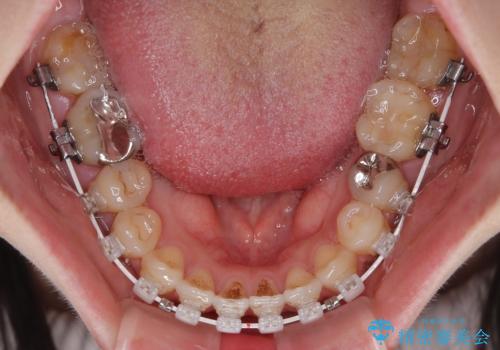

- 矯正装置

- 審美装置

- 治療期間

- 10ヶ月

治療開始から8ヶ月ほどで遠方への転勤が決まりましたが、歯列は概ね整っていたため、その後は東京出張を狙って治療を終える処置を行うことができました。